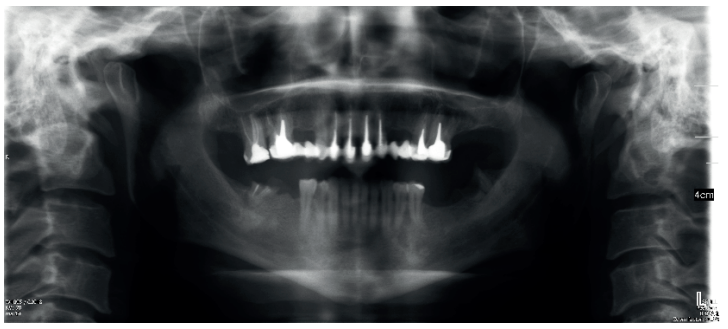

Diagnóstico radiográfico de los caninos maxilares incluidos. Comparación entre dos y tres dimensiones

Introducción: La inclusión de caninos tiene una alta incidencia y plantea varias complicaciones clínicas, siendo de vital importancia el diagnóstico precoz y exacto para minimizar los riesgos y complicaciones derivadas. El objetivo de este trabajo es analizar, utilizando como referencia las líneas planteadas por Alqerban, la efectividad de las dos dimensiones en el diagnóstico volumétrico de la inclusión de los caninos maxilares.

Métodos: Seleccionamos 27 pacientes con 36 caninos maxilares incluidos que se realizaron estudio de ortodoncia con ortopantomografía y tomografía computarizada de haz cónico (Cone Beam Computed Tomography, CBCT) del maxilar en la Clínica Universitaria de la Universidad Europea. Se trazaron tres líneas de referencia basándose en la distancia de la cúspide del canino al plano oclusal (L1), a la línea media (L2) y a su lugar ideal de erupción (L3), tanto en la ortopantomografía como en el CBCT. Como valores de referencia ideales seleccionamos un grupo control de 36 caninos maxilares erupcionados.

Resultados: Se compararon los resultados en dos y tres dimensiones mediante la prueba T de Student, tras comprobar su distribución normal mediante la prueba de contraste de Anderson-Darling. No se obtuvo significación estadística (p>0.05) para ninguna de las variables estudiadas.

Conclusiones: El uso del CBCT es vital para asegurar un buen diagnóstico en cuanto a la posición del canino y su relación con estructuras adyacentes y así establecer un plan de tratamiento adecuado. Aun así, la ortopantomografía aporta información suficiente para la planificación inicial.

Radiographic diagnosis of impacted maxillary canines: Comparison between two and three dimensions

Introduction: An impacted canine is a very common condition and raises several clinical complications. Early and exact diagnosis is important in order to minimise the risks and subsequent complications. The objective of this study is to analyse the effectiveness of two dimensions in the volumetric diagnosis for impacted maxillary canines, using the lines proposed by Alqerban as a reference.

Methods: An orthodontic study of the maxilla using orthopantomography with cone beam computed tomography (CBCT) at the Madrid European University Clinic was performed on 27 patients selected with 36 maxillary impacted canines. Three reference lines were drawn based on the distance from the cusp of the canine to the occlusal plane (L1), to the midline (L2) and to its ideal eruption site (L3), in both the orthopanthomography and the CBCT. As ideal reference values, we selected a control group of 36 erupted maxillary canines.

Results: The results were compared in 2 and 3 dimensions using the Student’s t test, after verifying their normal distribution using the Anderson-Darling contrast test. Statistical significance (p > 0.05) was not obtained for any of the variables studied.

Conclusions: The use of CBCT is vital to ensure good diagnosis of the canine position and its relationship with adjacent structures and thus establish an adequate treatment plan. However, orthopantomography provides sufficient information for initial planning.